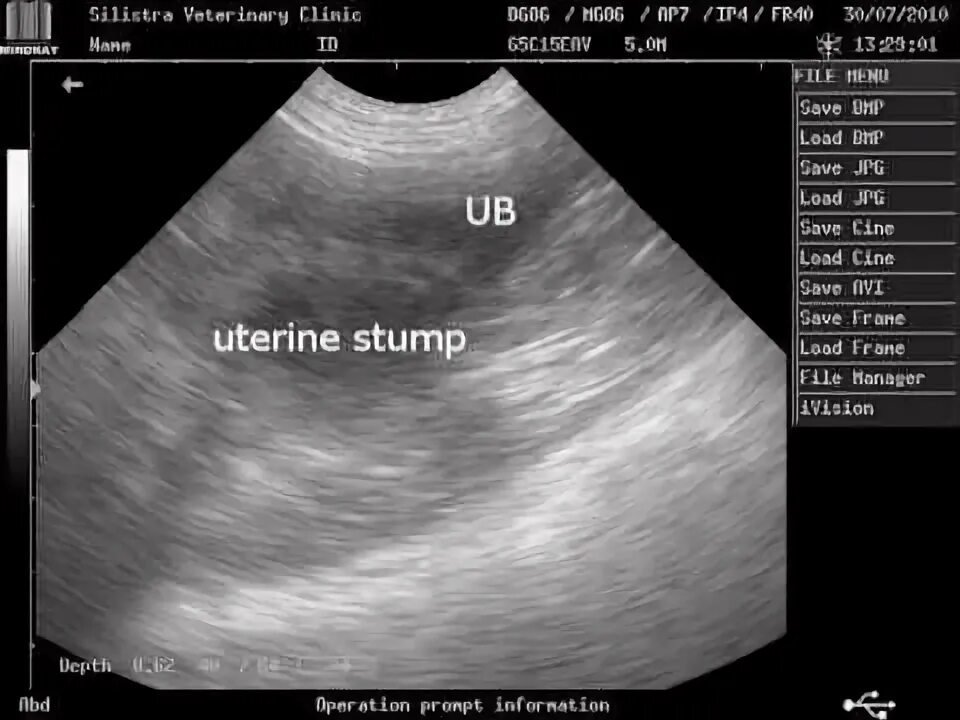

Гематометра симптомы